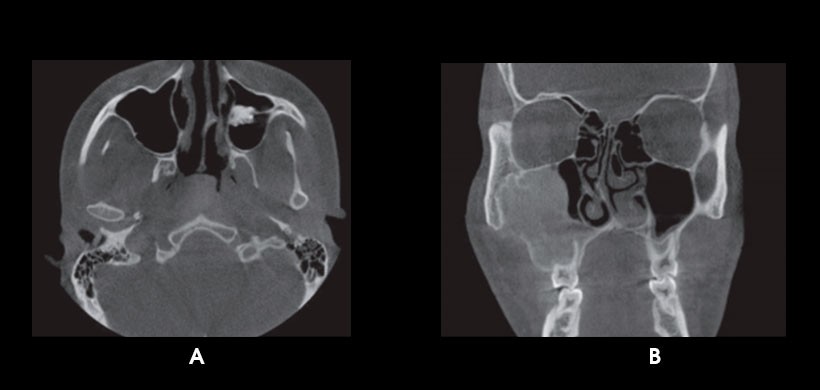

Fig 1. CBCT. A) Aplasia del seno esfenoidal derecho. B) Hipoplasia del seno frontal derecho.